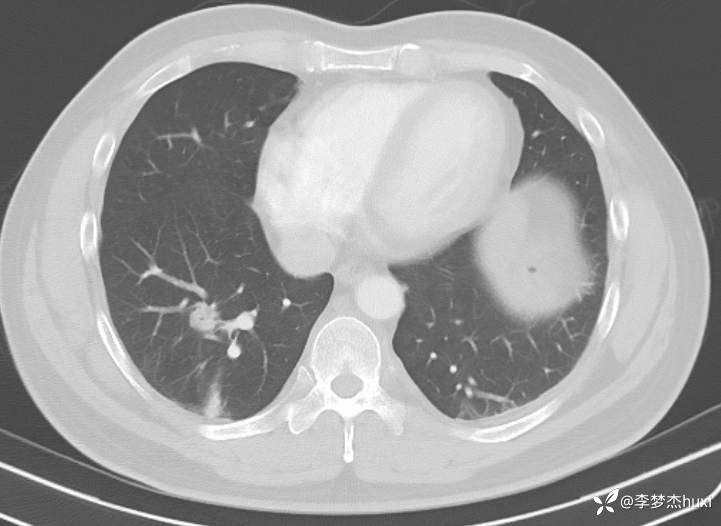

1.现病史:患者中年 男,缘于入院前20余天,患者体检,查胸部CT示肺结节(未见报告单),无发热,无咳嗽咳痰,无胸闷憋气,无胸痛,无呼吸困难及咯血等不适,未予治疗,1天前于我院复查胸部CT:右肺下叶结节—占位?右肺实性结节,建议复查或肺结节门诊会诊检查,右肺下叶索条,双肺纹理增重,气管憩室,双侧部分肋骨局部欠规整且密度增高,胸骨骨折,左肾局部密度减低,左肾高密度囊肿?请结合超声或结合增强CT检查。为手术治疗,门诊查体后以“肺结节”收住院。

4.辅助检查:胸部CT:右肺下叶结节—占位?右肺实性结节,建议复查或肺结节门诊会诊检查,右肺下叶索条,双肺纹理增重,气管憩室,双侧部分肋骨局部欠规整且密度增高,胸骨骨折,左肾局部密度减低,左肾高密度囊肿?请结合超声或结合增强CT检查。

1.右肺下叶 肺占位性病变 癌?炎症?;2.胸骨骨折;3.肋骨骨折。